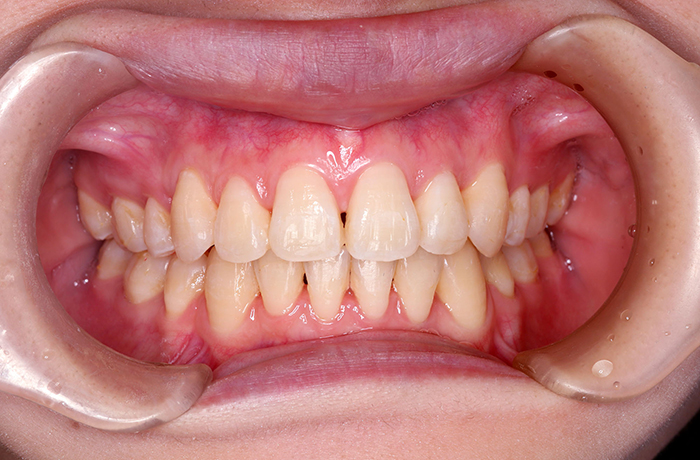

治療前

before

患者の症状 上顎前歯の凸凹

治療方法 非抜歯で、マウスピース型カスタムメイド矯正歯科装置による矯正

治療結果 歯並び、咬み合わせが良くなりました。

その他治療に関する情報 歯並びをより良くするために追加でアライナーを発注しました。

リスク/副作用 スペース不足を解消するために歯と歯の間をわずかに削合しました。